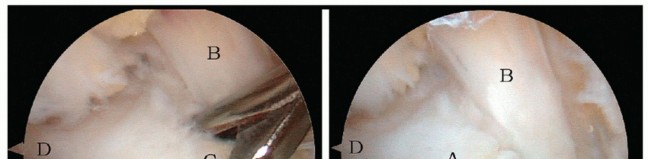

Removing the ▪ Care should be taken not to place the chisel too far anterior, so as to avoid

hypertrophic posterior talar process using the chisel

entering the subtalar joint (FIG 5).

FIG 5 • A,B. Removal of the hypertrophic posterior talar process using the chisel. Care should be taken not to place the chisel too far anterior, so as to avoid entering the subtalar joint. FHL , flexor hallucis longus; OT , os trigonum.